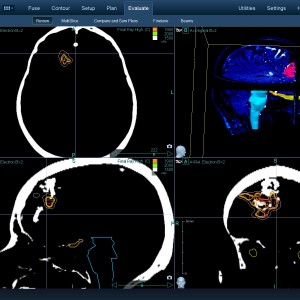

Στις παρακάτω φωτογραφίες θα δείτε παραδείγματα πλάνων θεραπείας καρκινικών όγκων με CyberKnife. Παρατηρήστε πόσο κοντά στους υγιείς ιστούς βρίσκονται οι καρκινικοί όγκοι που χρειάζεται να ακτινοβοληθούν. Μόνο με το CyberKnife και το προσωπικό πλάνο θεραπείας, μπορούν να ακτινοβοληθούν οι όγκοι χωρίς να πληγούν οι παρακείμενοι υγιείς ιστοί.

Παρατηρήστε τις πάρα πολλές δέσμες του CynerKnife που ακτινοβολούν τους όγκους από διαφορετικές γωνίες ώστε να μην προσβληθούν από την ακτινοβολία οι υγιείς ιστούς.